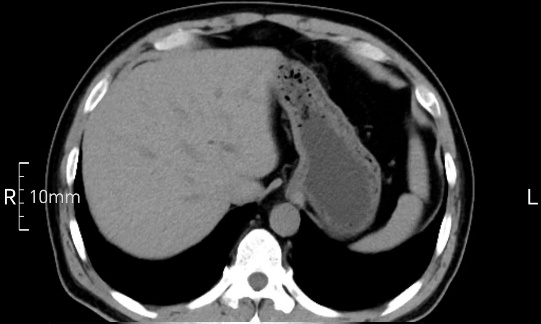

看看下面三幅便知遵醫(yī)囑的重要性。

完美禁食且喝飽飽,胃壁完美展現(xiàn)。

CT檢查前的“禁食”和“喝飽”,看似矛盾,實則合情合理,分工合作:空腹:是為了讓上腹部(肝膽胰脾腎等)的圖像清晰無干擾,并保障檢查安全。喝水:有效的充盈胃部和、腸道使圖像清晰呈現(xiàn)。兩者巧妙配合,都是為了給您一個最精準(zhǔn)的診斷結(jié)果。